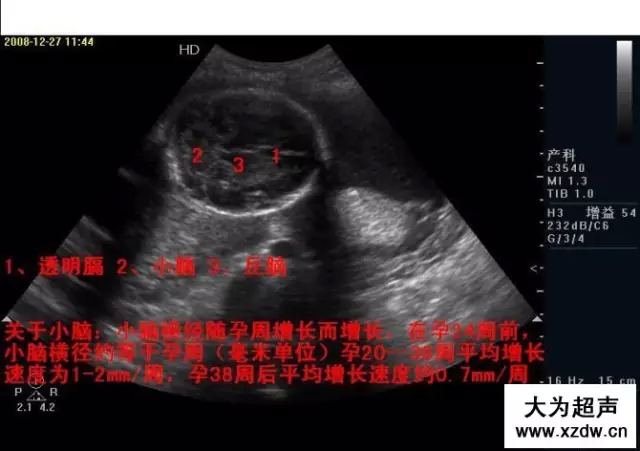

新領(lǐng)程大為超聲 早中孕期胎兒

產(chǎn)科超聲正常圖片